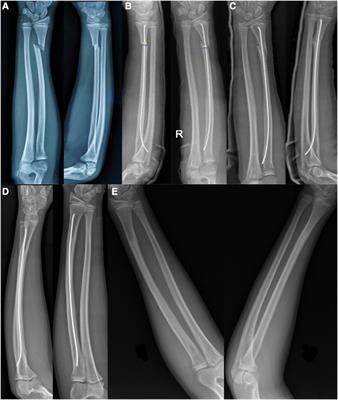

Our expert trauma team provides comprehensive fracture and injury management with advanced techniques and personalized care.

Simple Fractures – Treated effectively with splinting or plaster of paris application 24X7

Compound Fractures – Specialized care to prevent infection and restore function.

Major Fractures – Multimodal treatment to stabilise the patient immediately and team work to stabilise the fractures and other associated injuries (Head injuries, abdominal injuries)

Periprosthetic Fractures – Expert management of fractures around Prosthetic joints .

Fractures in Children – Gentle, specialized treatment for growing bones including surgical and non surgical methods.

Hand Injuries – Comprehensive care for hand trauma to restore mobility.

Hand – Tendon Injuries – Skilled repair and rehabilitation for tendon damage.